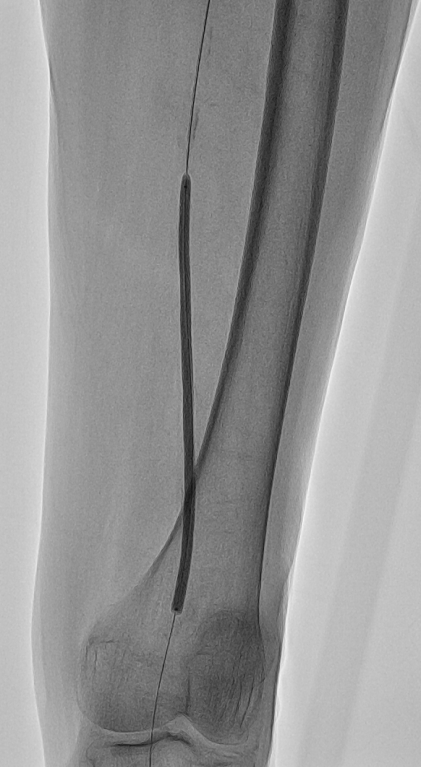

造影术中顺左股动脉走向穿刺,置入6F鞘管,造影提示“左股浅动脉中远段完全闭塞(图1),可见明显钙化影,左股深动脉可见侧枝至左腘动脉;左胫前动脉近段完全闭塞(图2),左胫后动脉开口完全闭塞,左腓动脉近段闭塞,左胫前动脉近段侧枝至左腓动脉中段,左腓动脉中段至足背动脉轻度狭窄,血流缓慢”。

图1 左股浅动脉中段闭塞